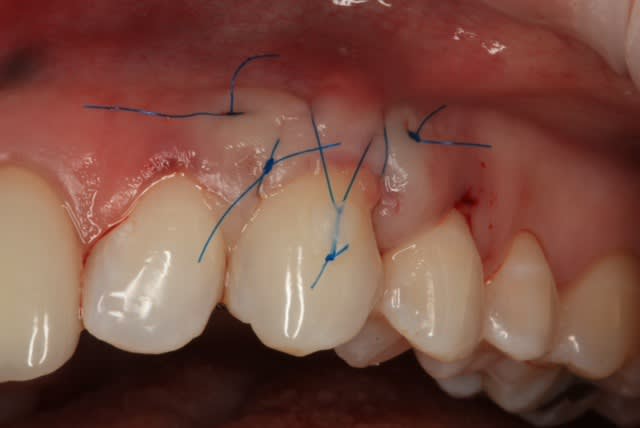

Il y a une "sling suture" pour la traction, le point collé au compo, est en plus, pour tester ;-)

Voici un cas similaire, encore une 23, perte de tissu plus grande, pas de point suspendu avec compo, seulement 2 "sling-suture".

Greffon tracté sous lambeau en mésial et distal comme le cas précédent avec sutures.

Pas d'incision vertical en mésial, surtout que la 22 est un implant, placé trop apical, donc risque de perdre papille distal de 22 +++. Petite incision vertical en distal de 23, pour tracter le lambeau.

Photo final à 4 mois, belle intégration du tissu je pense.